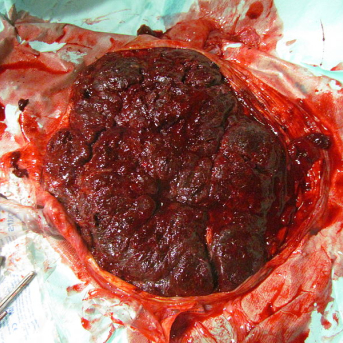

O parto é um momento único da vida e de grande importância para todas as mulheres. Durante...